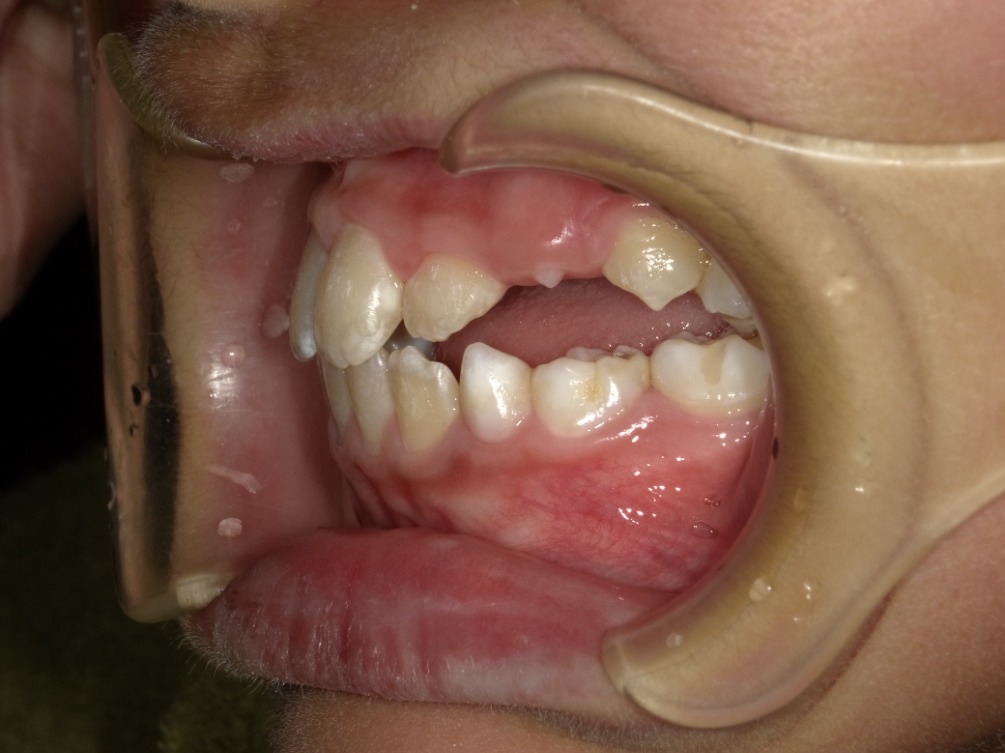

右横

| 治療内容 | インビザライン・ファースト |

|---|---|

| 治療詳細 | 反対咬合や叢生、開咬を整えるために、歯の表面にアタッチメント(白い突起)をつけました。 また、顎間ゴムと呼ばれる引っ掛けるゴムの補助装置も用いて治療を行いました。 |

| 患者情報 | 10代 男性 予防矯正から移行 |

| 主訴 | 受け口 |